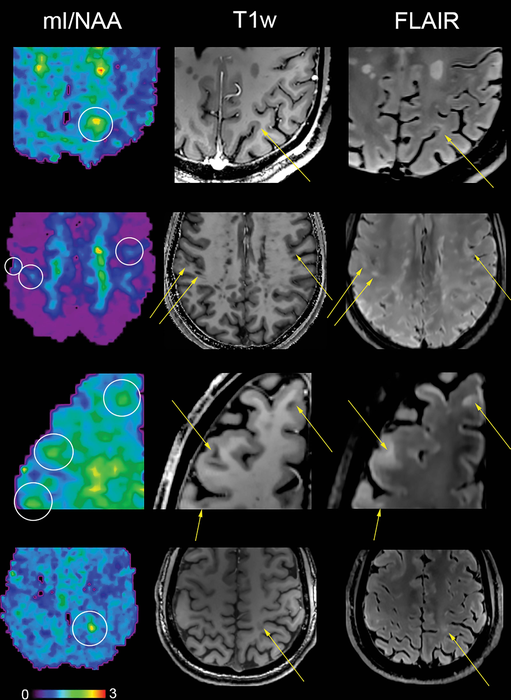

*Proton MR Spectroscopy Detects Brain Changes in MS Patients *

*New MRI Technique Detects MS Brain Changes Earlier | Imaging *